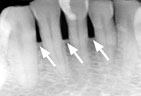

Gum disease is usually caused by plaque, a sticky film of bacteria that constantly forms on teeth. If plaque is not removed with thorough daily brushing and cleaning between teeth, gums become irritated and inflamed. The irritated gum tissue can separate from the teeth and form spaces called pockets. Bacteria move into the pockets where they continue to promote irritation. Left untreated, the process can continue until the bone and other tooth-supporting tissues are destroyed. The early stage of periodontal disease is called gingivitis. It often results in gums that are red and swollen and may bleed easily.

Periodontitis Periodontitis